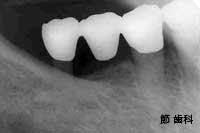

⑧ これは、右下の6番目の歯の中間欠損部分に、スクリュータイプの“人工サファイヤ”インプラントを埋入し、前後の歯とブリッジ状に連結する事で欠損補綴を行った症例です。

info_1